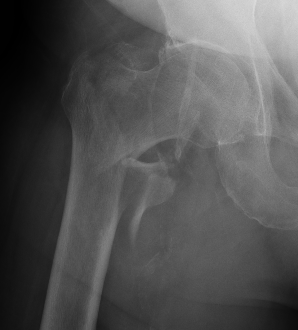

Isolated GT Fracture

Dynamic hip screw

Mechanism

Plate is a lateral tension band whilst the sliding screw allows controlled fracture impaction

Cephalomedullary nail / Proximal femoral nail

Mechanical advantages

- load sharing rather than load bearing

- decreases lever arm

- supports medial cortex

Indications

- reverse oblique

- unstable fracture / loss of lateral buttress / loss posteromedial support

- subtrochanteric extension